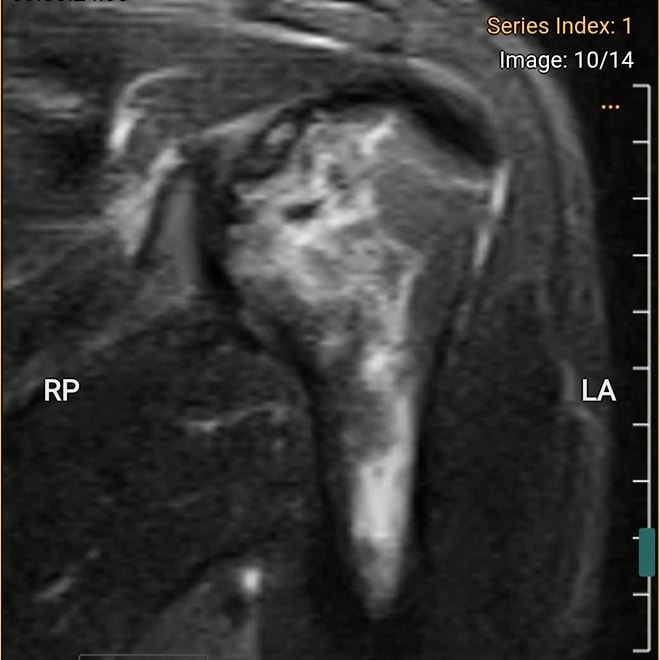

Hình ảnh chụp MRI cho thấy bệnh nhân bị hoại tử chỏm xương cánh tay trái, ổ hoại tử lan xuống vùng cổ và thân xương cánh tay.

Kết quả chụp MRI cho thấy phần chỏm xương cánh tay trái bị hoại tử, ổ hoại tử lan xuống vùng cổ và thân xương cánh tay. Khi chụp X-quang phần khớp háng nhận thấy dấu hiệu hoại tử vô mạch chỏm xương đùi hai bên độ 2 theo ficat và alert (tình trạng tế bào xương ở chỏm xương đùi chết đi do mất nguồn cung cấp máu).